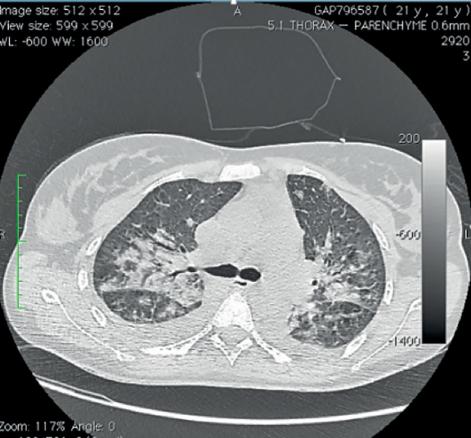

Le scanner cervico-thoracique (fig. 1 et 2 ) montre une thrombose de la veine jugulaire interne gauche ainsi qu’un épanchement pleural bilatéral et une pneumopathie des deux côtés sur emboles septiques, permettant de poser le diagnostic de syndrome de Lemierre.

Le scanner cervico-thoracique (

L’aspect radiologique typique est celui de notre observation. Les abcès pulmonaires, multiples et disséminés par voie hématogène, sont évocateurs. Ils font rechercher une thrombose jugulaire ou de ses collatérales.